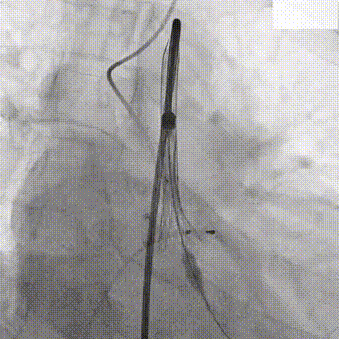

主动脉根部造影

20mm TaurusAtlas球囊

输送系统过弓

确定初始释放位

瓣膜稳定释放至工作位

TaurusOne AV23mm瓣膜瓣下3-4mm 工作位造影

瓣膜完全释放

瓣膜位置理想